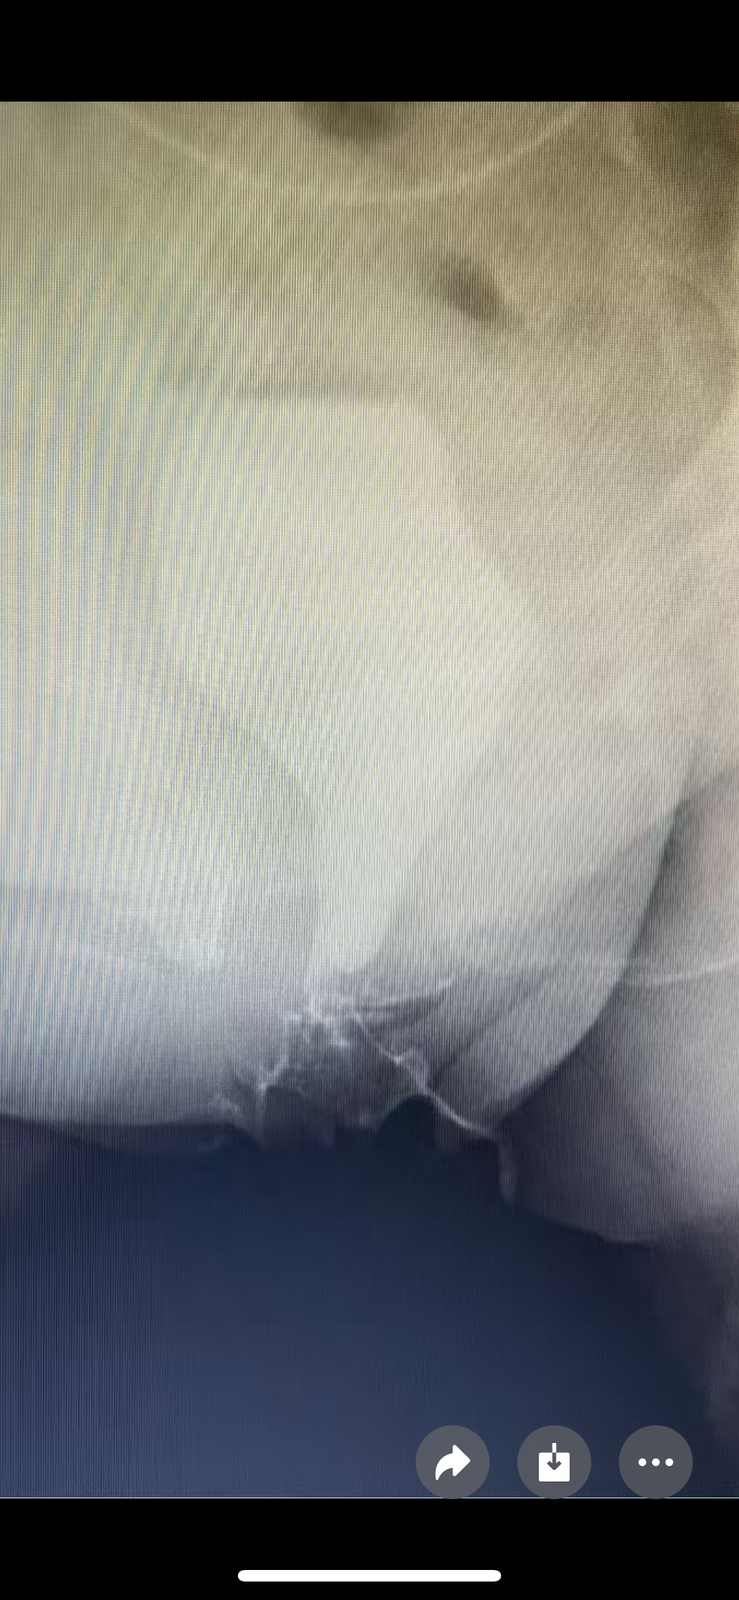

3. 影像“透视*:盆腔MRI(判断肿瘤范围) 、尿道造影可看到梗阻情况